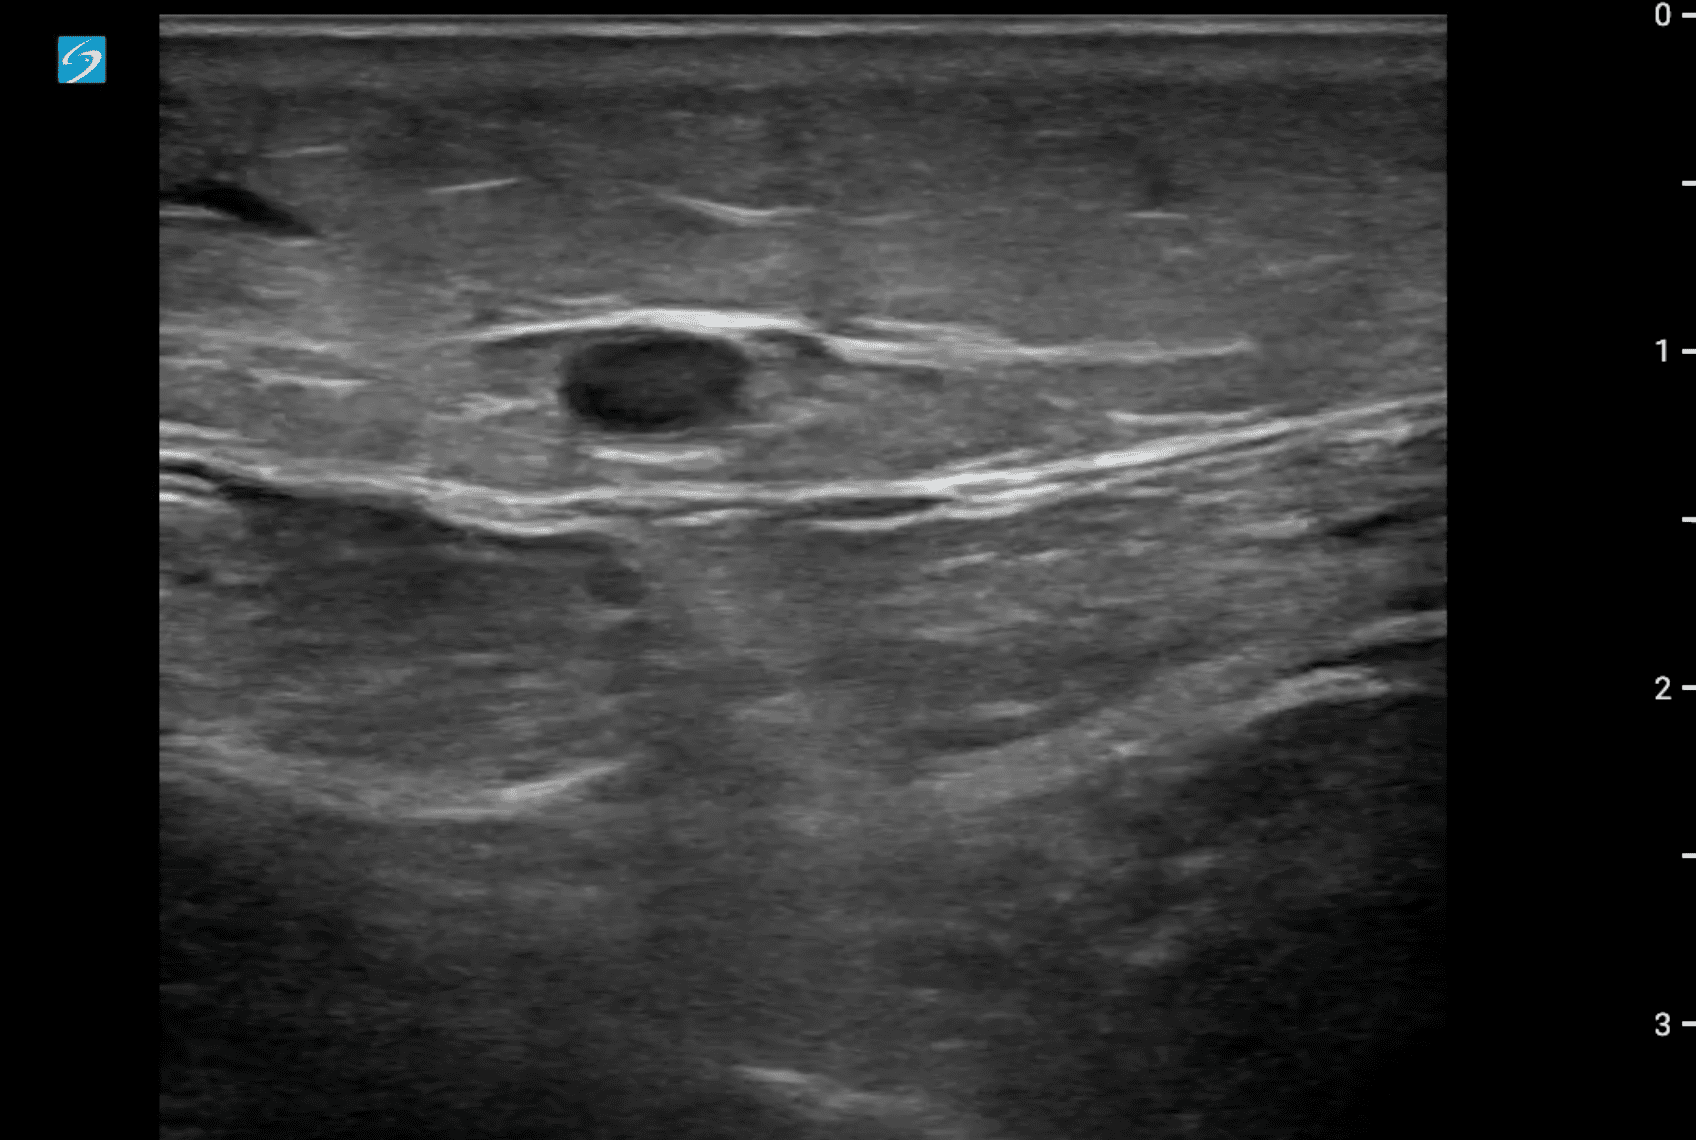

Hallazgos ecográficos

Se localiza ecográficamente la vena femoral común con una imagen hipoecogénica que no colapsa con a la compresión y que se extiende por femoral superficial hasta poplítea. Tras hallazgos, se realiza también una ecografía cardíaca, con un diámetro de visu VD/VI < 1 y con una función cardíaca conservada, con resultado en escala PESI de riesgo bajo.

Como diagnóstico diferencial se valoran celulitis e insuficiencia venosa crónica. Se realiza una ecografía reglada que confirma el diagnóstico de sospecha de trombosis venosa profunda (TVP) extensa subaguda.